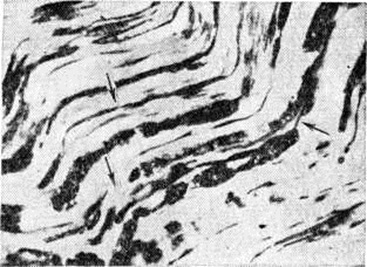

Рис. 3.

Гистотопограмма тонкой кишки при странгуляционной непроходимости (продольный разрез): 1 — приводящий отдел кишки; некроз (2) стенки кишки в зоне борозды ущемления; 3 — отводящий отдел кишки; окраска гематоксилин-эозином; × 50.